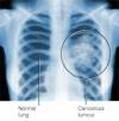

Tác dụng trên ung thư phổi tế bào nhỏ:

Khi thử nghiệm artemisinin trên những tế bào của ung thư phổi tế bào nhỏ theo thể nhạy (H69) và đa kháng thuốc (H69VP), thuốc artemisinine đượnc tiêm cùng lúc transferrin để tăng nồng độ sắt, người ta thấy rằng hiệu ứng gây độc tế bào (cytotoxicity) của artemisinin đối với các tế bào H69VP thấp hơn 10 lần so với các tế bào H69. Vấn đề này kết luận rằng artemisinin là một phần vào kiểu hình kháng thuốc. Thử nghiệm này cũng chỉ ra trước khi điều trị các tế bào H69 không có nồng độ sắt thấp hơn đối với artemisinin ngược lại đối với các tế bào H69 VP, nồng độ sắt lại thấp hơn gần bằng với mức nhạy của thuốc. Do vậy, các nhà khoa họckết luận rằng artemisinin có thể sử dụng cùng với transferin trong điều trị kháng thuốc điều trị ung thư phổi tế bào nhỏ. (Sadava, D et al, Transferrin overcomes drug resistance to artemisinin in human small cell lung carcinoma cells, Cancer Letter, 179,151-156, 2002)